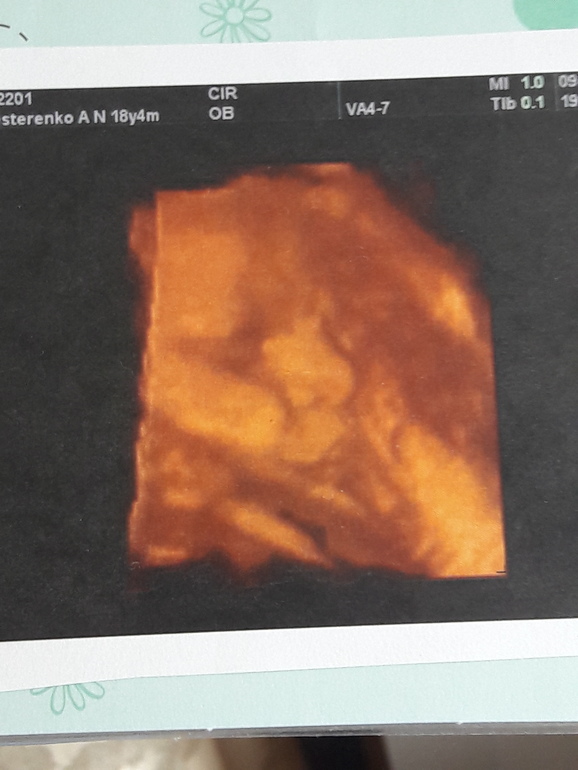

Там движение вам покажут в обычном 2д,а в 3д фотку просто сделают))вот сегодня была-29ая

уже видно,что на старшего сына похож только носом😂не похожи,хотя родные братья

Более менее не инопланетянин после 20 недели. У нас было так, что врач сначала делает само УЗИ стандартное, всё измеряет все объясняет и показывает, а в конце в качестве развлечения уже переключает на аппарате на 3D и мы смотрим, делает снимки если ракурсы хорошие

Я думаю тут индивидуально - зависит от врача и от клиники. У нас всё УЗИ наверное минут 20-30 заняло, а 3D в конце ну минут 5 наверное. Смотря ещё как лежит..с сыном мы никак не могли лица поймать на 3D а на остальное и смотреть не интересно)) он утыкался лицом в стенку матки и всё тут..доча более сговорчива, видимо как все девочки любит фотать😁